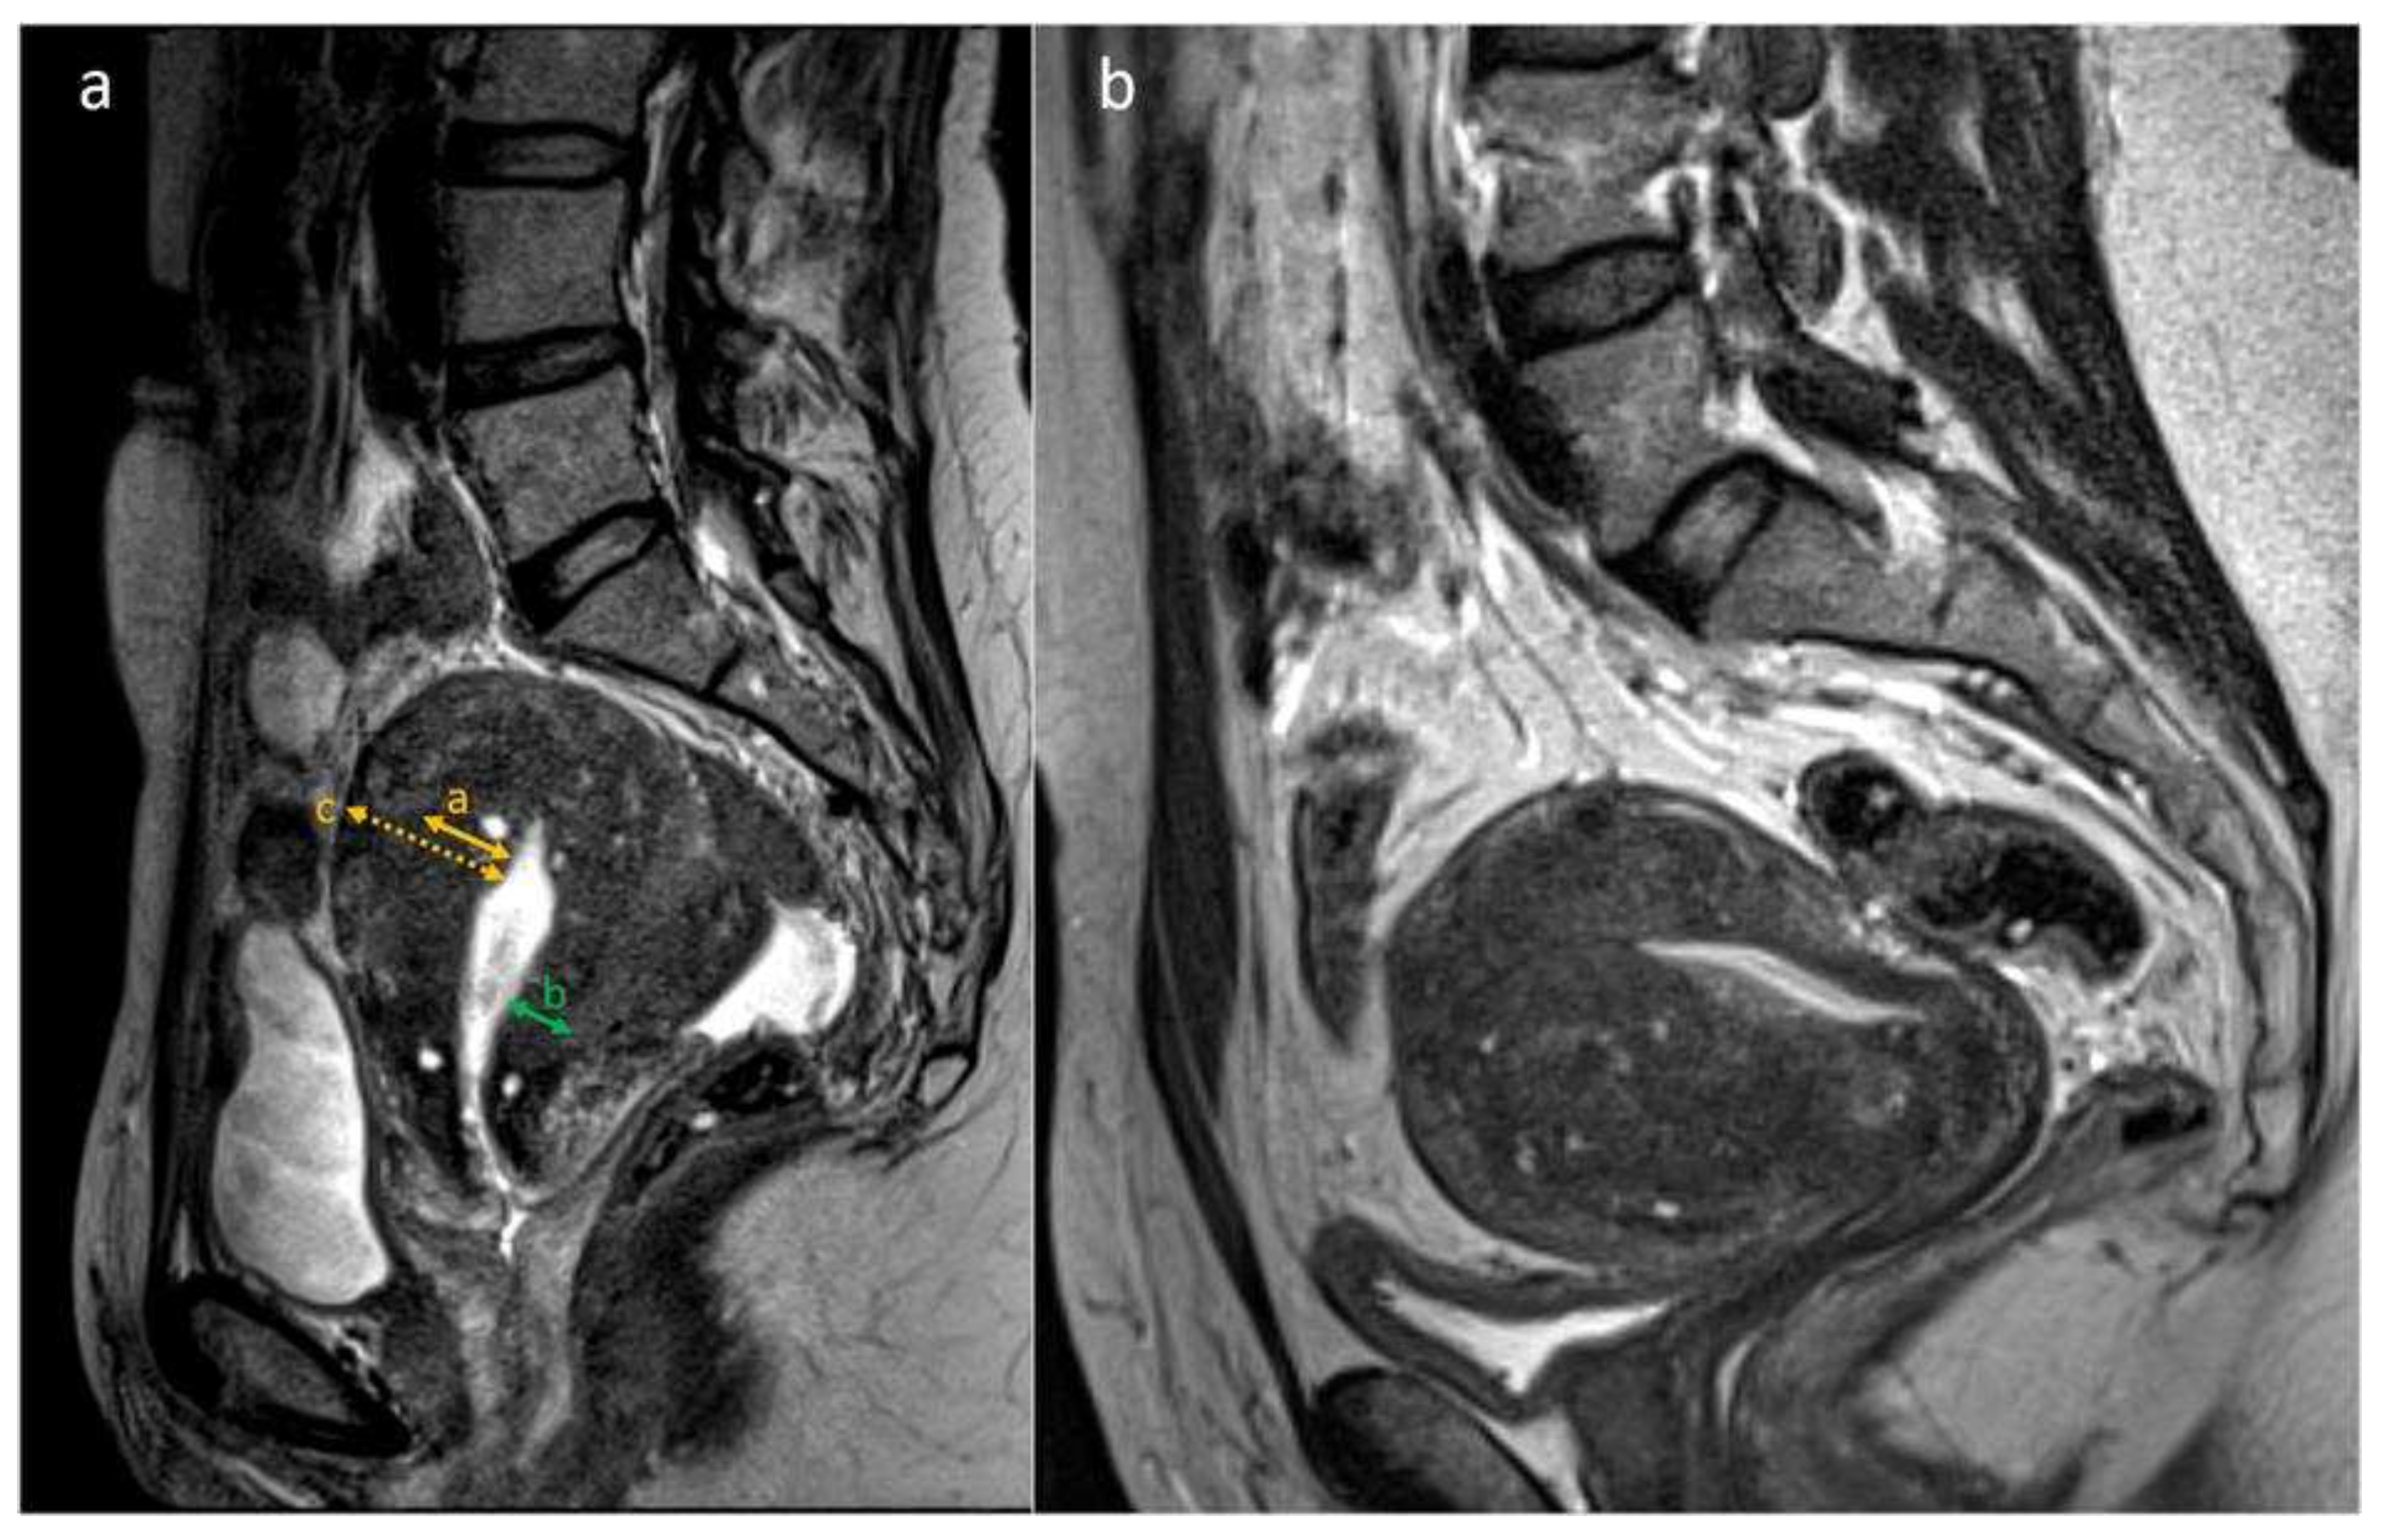

Figure 1. a-b. MRI features of adenomyosis: T2-weighted sagittal images from two different subjects with adenomyosis. Figure 1a. JZmax, the thickest part of the JZ in the midsagittal plane (orange double arrow). JZmin, the thinnest part of the JZ in the midsagittal plane (cervix excluded) (green double arrow). Myometrial thickness, measured at the same level as JZmax (orange dotted double arrow). Figure 1b. Example of a uterus with globular shape and asymmetric thickening of JZ (anterior JZ thicker than posterior JZ). The JZ is irregular due to the presence of multiple hyperintense cystic foci within the thickened JZ.

The images were pseudonymized and evaluated on a Picture Archiving and Communication System (PACS; IDS7 version 21.1, Sectra AB, Linköping, Sweden) at the Karolinska University Hospital by four experienced radiologists. Raters could save their assessments and resume at a later time, to reduce risk of fatigue. With regard to the presence or absence of adenomyosis, each rater based the assessment on their subjective evaluation of the radiological features. There were no standardized criteria given on when to make the diagnosis. The predefined MRI features assessed are listed in Table 1 and shown in Figure 1.